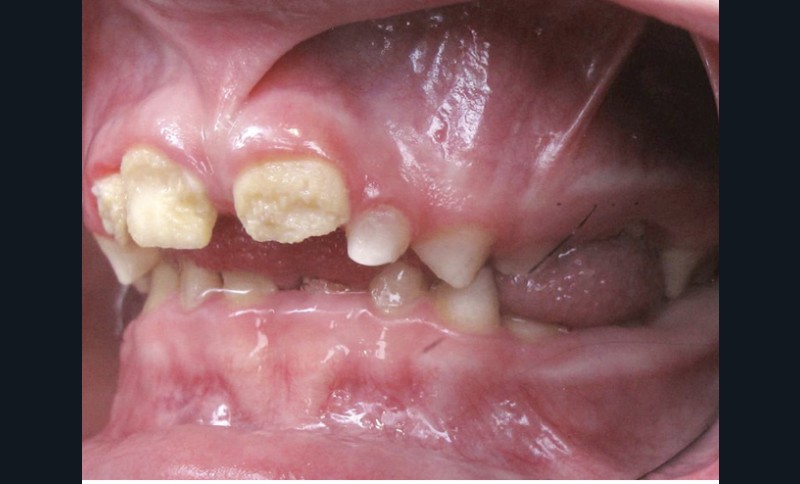

Il existe des anomalies dentaires (tabl. I) [1-12], mais aussi occlusales associées aux AI (fig. 1 et 2).

Selon de nombreuses études, l’anomalie occlusale la plus fréquemment retrouvée en association avec les AI est l’infraclusion antérieure, puisqu’elle est retrouvée chez 22 à 64 % des patients présentant cette affection, et encore plus chez les femmes [2,8,13-19]. Cette anomalie touche tous les types d’AI mais à des degrés très divers. Son incidence semble élevée dans les formes hypominéralisées, moindre dans les formes hypoplasiques et nettement moindre dans les formes hypomatures [8,17,18]. La sévérité de l’atteinte amélaire ne semble pas corrélée avec la présence ou l’intensité de cette malocclusion [17].